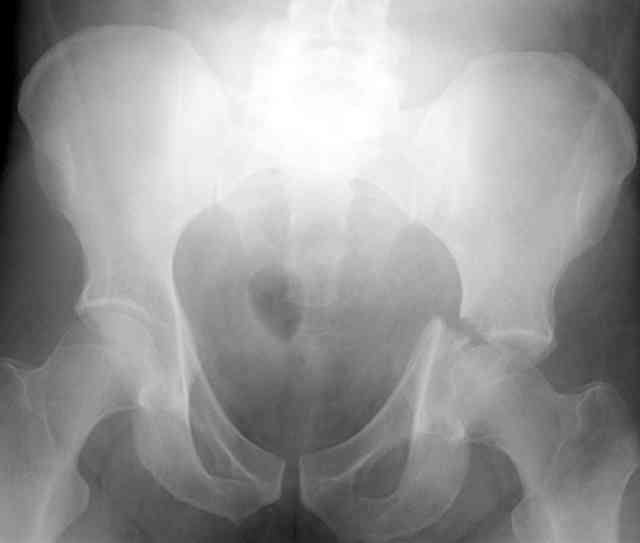

the case that I found is a 20yo male, MCC. his AP pelvis shows an interesting position of his bladder. it is pushed aside by a hematoma from SGA injury. we did a limited lateral window approach for the anterior column first, pt bumped up/supine. then closed and repositioned for KL. I could not find intra-op photos of cases when we did only a small incision for the AC screw (but they do exist!!). the lateral window is available for reduction assessment if a KL approach is being used. in the lateral position this window is available. the prone position definitely takes pressure off of the post column and facilitates reduction. in the lateral position a schantz pin in the ischial tub +/- bone hook in sciatic notch helps with PC reduction. the lateral position also gives better airway access for anesthesia. airway problems are rare, but prone position seems to be a bit more of a challenge to exchange the tube, or reintubate altogether. just something further to debate!